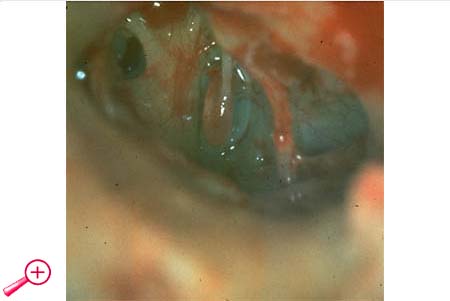

In diesem Fall fehlt der lange Ambossfortsatz.

Ein mikrochirurgischer Eingriff lohnt sich bei den kleinen Missbildungen meistens!